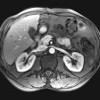

Зондовая энтерография

Зондовая энтерография. Метод визуализации кишечника с использованием рентгеновских лучей и дополнительных инструментов, в ходе которых специалист получает серию черно-белых изображений и может отслеживать динамику моторики кишечника. Он используется для изучения состояния тонкой кишки, расположения и количества петель, ширины просвета, а также частей толстой кишки. Исследование проводится для обнаружения объектов различной природы. Процедура проводится для выявления воспалительных изменений, обструкции и структурных нарушений. Эта методика требует самостоятельной подготовки пациента в течение нескольких дней, выполняемой после прямого введения контрастного вещества в тонкую кишку с помощью специального зонда.